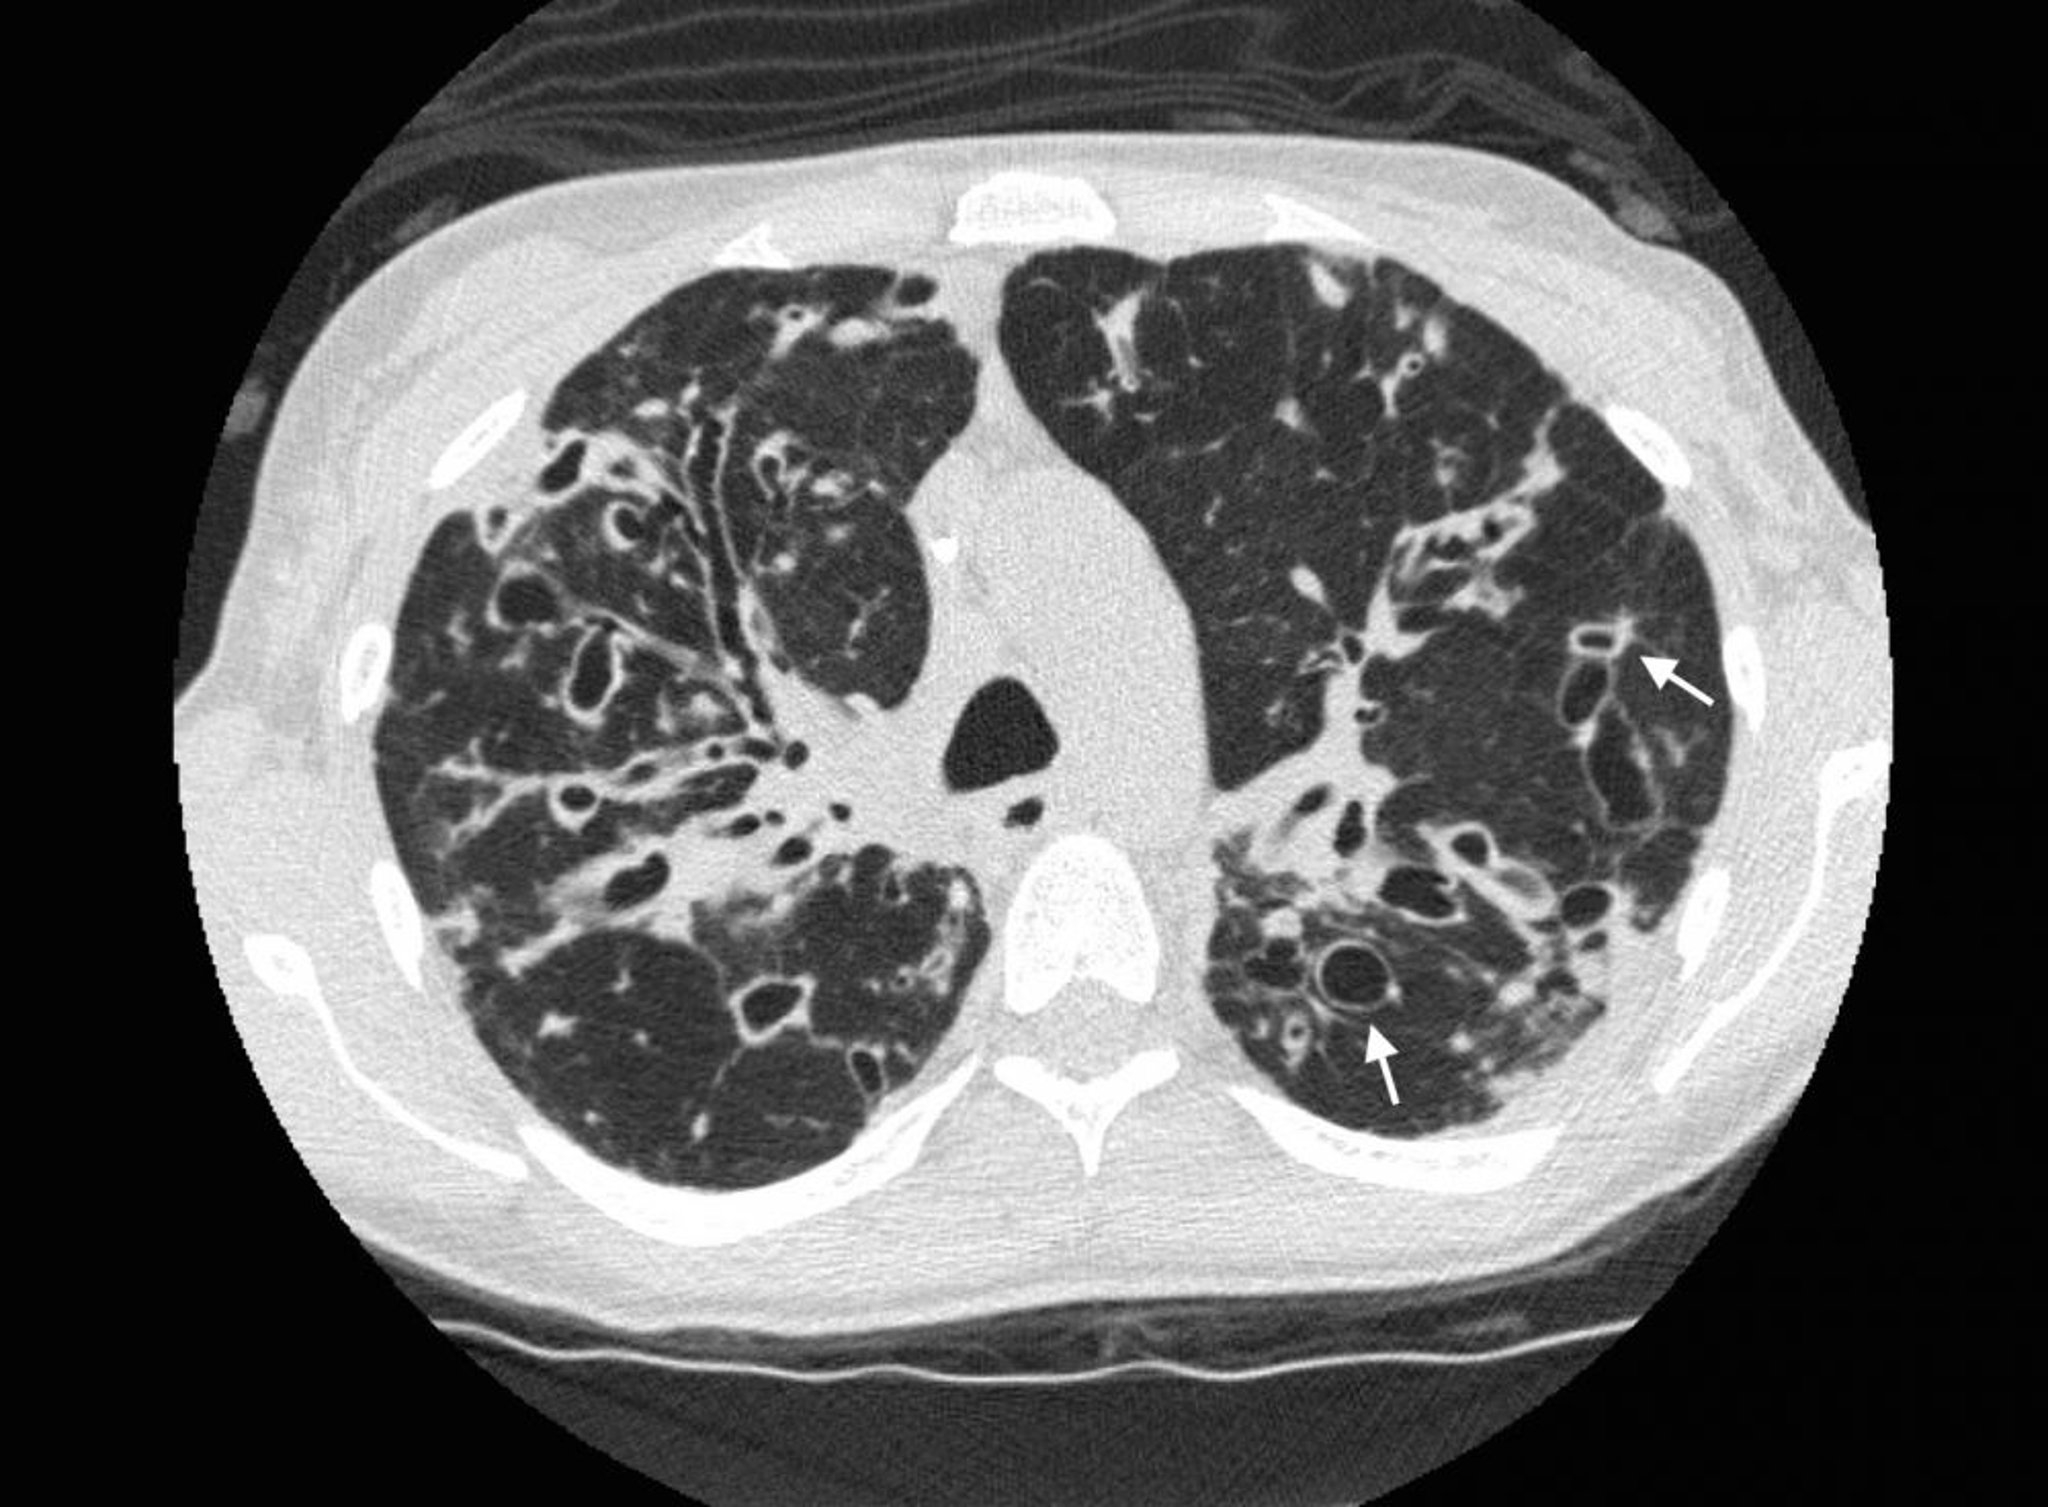

Bronchiektase (Computertomographie)

Ein Thorax-CT bei einem Patienten mit zystischer Fibrose zeigt eine schwere Bronchiektase in den oberen Lungenbereichen mit erweiterten Atemwegen und zystischen Veränderungen. Pfeile zeigen das Siegelringzeichen, bei dem ein erweiterter Atemweg (der Ring) an eine kleinere Arterie (die Spitze des Rings) angrenzt. Normalerweise sind die Atemwege gleich groß oder kleiner als die benachbarten Arterien.

Photo courtesy of Başak Çoruh, MD.